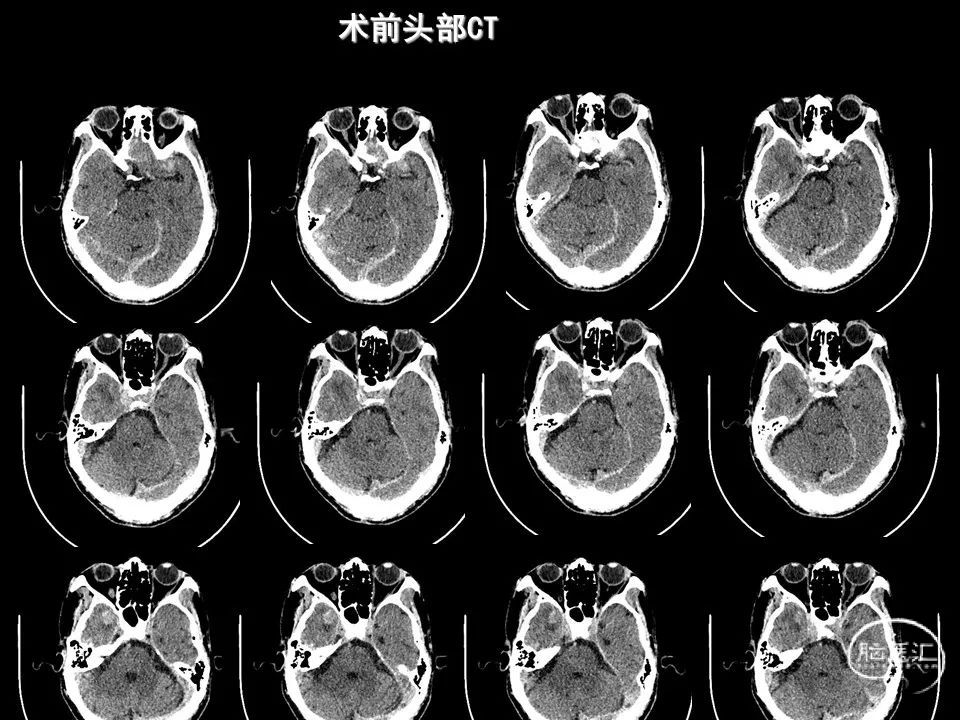

今天为大家分享的是《监测有道丨颅脑创伤-神经重症周刊》第338期,由海南省人民医院朱蔚林教授带来的:2例脑出血微创手术,欢迎阅读、分享。

主要从事神经内镜下垂体腺瘤、高血压脑出血手术,鞍区肿瘤,颅底肿瘤,脑膜瘤、听神经瘤、胶质瘤等显微外科手术,颅脑创伤,脑积水、蛛网膜囊肿、颅内感染等救治